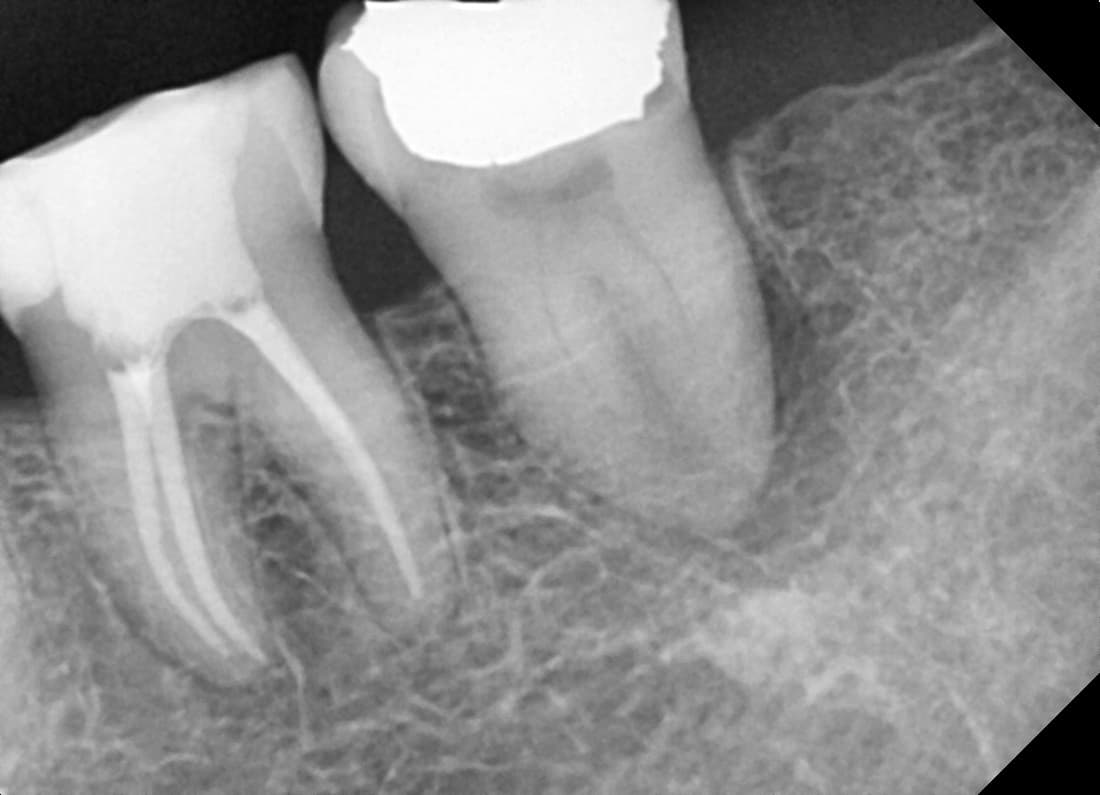

Periapical Lesion Healed

Molar with severe inflammation and pus

Before

After

Complete healing of periapical lesion 6 months after treatment